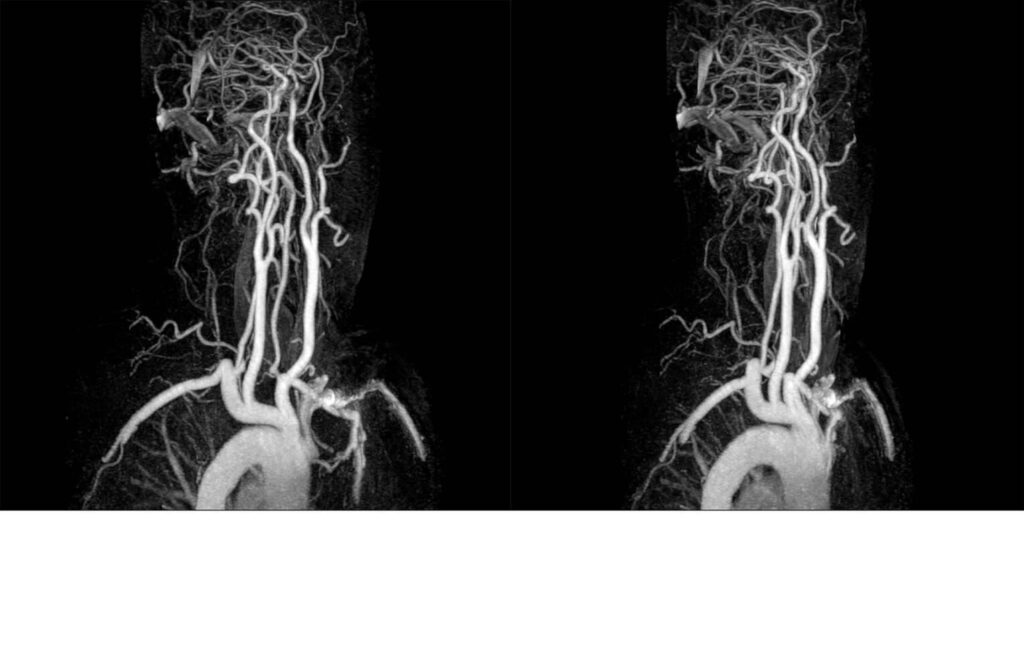

Die MRT-Phlebografie basiert prinzipiell auf der Methode der Magnetresonanztomographie (MRT). Dabei werden Schnittbilder des Körperinneren mittels starker Magnetfelder und Radiowellen angefertigt – also gänzlich ohne den Einsatz von Röntgenstrahlung. Diese zweidimensionalen Bilder können anschließend am Computer übereinandergelegt werden, wodurch ein dreidimensionaler Eindruck entsteht. So können die Venen in ihrem gesamten Verlauf dargestellt werden.

Bei der MRT-Phlebografie unterscheidet man die direkte Darstellung von der indirekten Phlebografie. Bei der direkten Methode wird zunächst eine Fußvene punktiert, über die in der Regel ein gadoliniumhaltiges Kontrastmittel gespritzt wird. Anschließend werden MRT-Aufnahmen angefertigt. Das sich das Kontrastmittel in den Venen anreichert, erscheinen diese auf den MR-Aufnahmen dann deutlich heller als die umliegenden Gewebe. So lassen sich die Gefäße einerseits gut abgrenzen und andererseits werden so – durch eine Kontrastmittelaussparung – auch etwaige Thrombosen sichtbar.

Die MRT ist eine hochpräzise Untersuchungstechnik, weshalb nicht nur größere Auffälligkeiten sichtbar werden, sondern sich auch bereits kleinste Veränderungen sicher erkennen lassen. Schließlich kann durch spezielle Computerprogramme auch ein dreidimensionaler Datensatz erzeugt werden, bei dem die umliegenden Gewebe entfernt werden, sodass ausschließlich die Gefäße gezeigt werden. So können diese isoliert vom Rest des Körpers bis ins letzte Detail beurteilt werden.

Bei der indirekten MRT-Phlebografie hingegen ist die Gefäßdarstellung gänzlich ohne Kontrastmittel inzwischen möglich. Durch verschiedene spezielle MRT-Methoden können physikalische Eigenschaften und Unterschiede des Blutes genutzt werden, um eine kontrastverstärkte Darstellung der Gefäße zu erreichen.